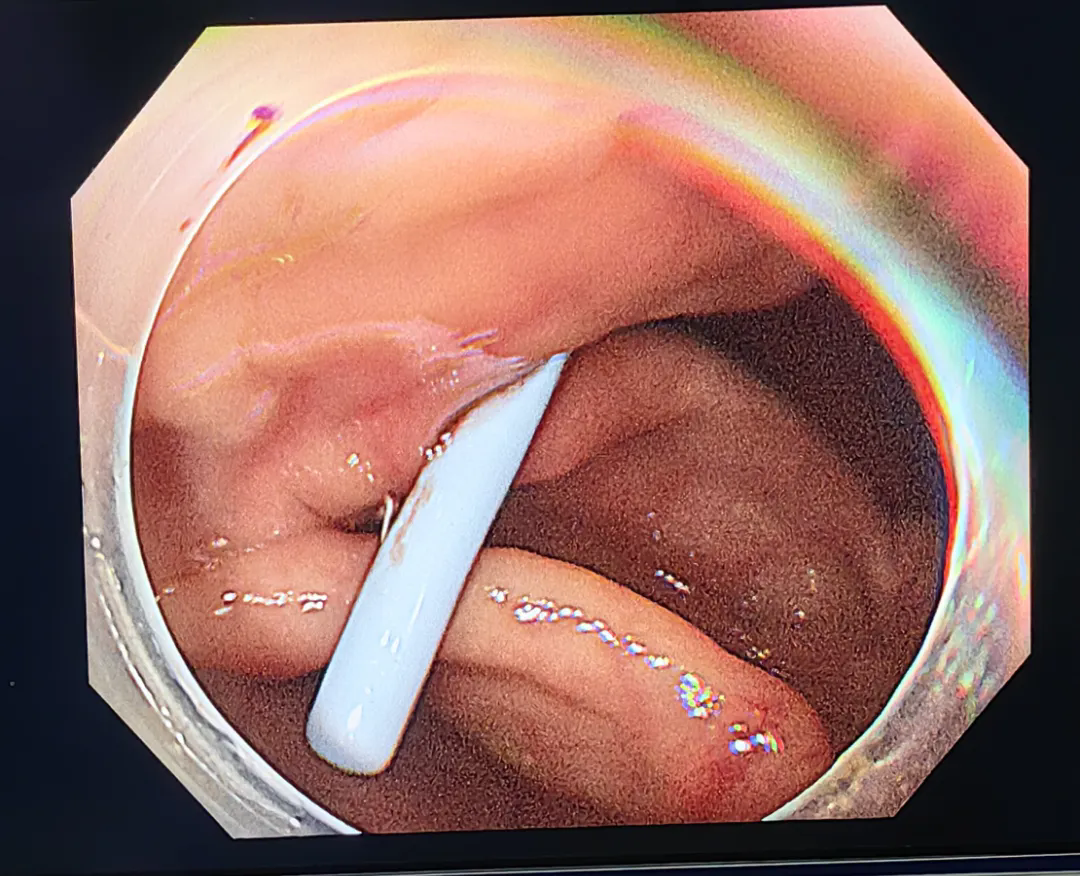

完善術(shù)前相關(guān)準(zhǔn)備,在麻醉科、內(nèi)鏡中心醫(yī)護(hù)人員的全力配合下,由李海菊主任、劉繼威主治醫(yī)師及楊國(guó)帥主治醫(yī)師等人組成的手術(shù)團(tuán)隊(duì)為劉先生實(shí)施了內(nèi)鏡下闌尾糞石取出術(shù)+內(nèi)鏡下逆行闌尾腔沖洗術(shù)+內(nèi)鏡下闌尾支架置入術(shù),術(shù)中通過(guò)沖洗、引流、網(wǎng)籃套取等操作,將嵌頓于闌尾腔內(nèi)的糞石取出,并放置支架一枚引流,術(shù)后患者腹痛明顯緩解,麻醉清醒后即可下地行走并恢復(fù)進(jìn)食。

網(wǎng)籃取石